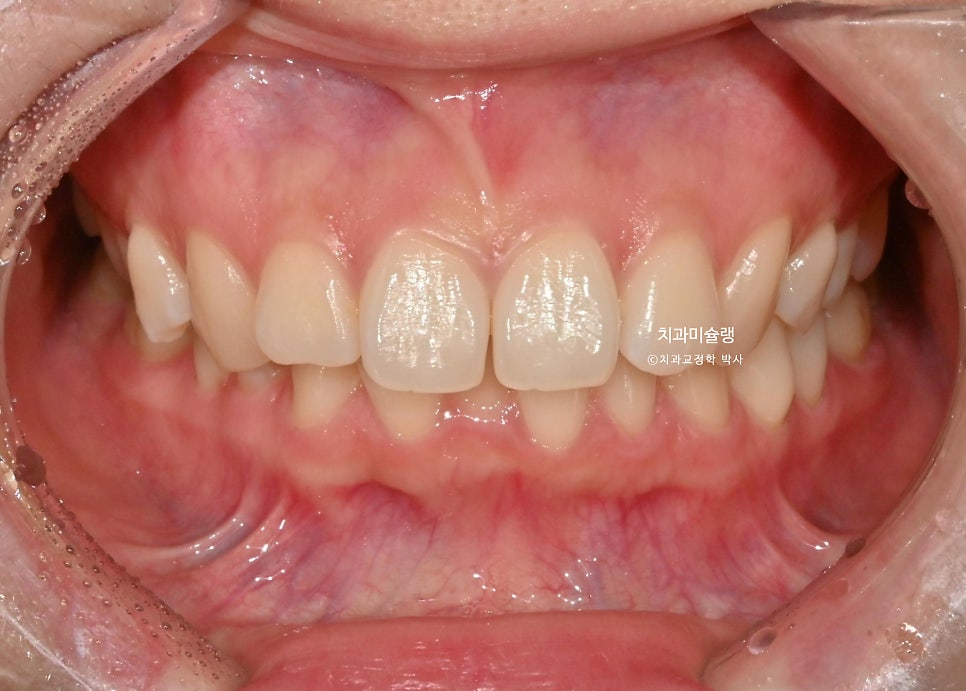

최종 치료 결과 – 2026년 3월

어금니 교합은 물샐틈 없는 1급 교합관계를 보입니다.

작은어금니 회전까지 완벽 개선되었습니다.

전체 치료기간은 9개월, 재제작은 1회 했습니다.

안으로 쓰러져 있던 위 송곳니각도가 개선되었습니다.

들쑥날쑥했던 아래 앞니 잇몸 라인도 치아 높낮이가 조절되면서 자연스럽게 대칭이 맞아졌습니다.

중심선도 상당히 개선되었죠.

돌출된 윗니가 뒤로 들어가며 위아래 앞니 사이 간격이 줄었습니다.